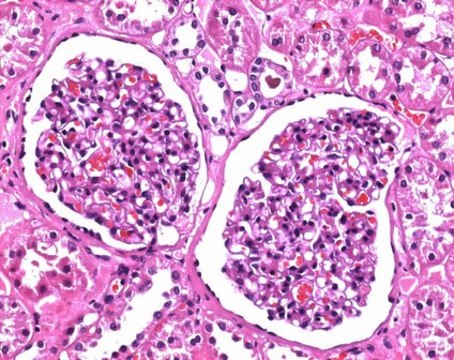

histology

组织学属于生物学和医学领域,是专门阐明组织结构、功能和病理状态的学科。其技术原理涉及使用各种经过靶标针对性优化的化学染色剂来研究单细胞生物、植物、真菌和动物的组织样本。

Learn about the criticality of biological tissue staining for research and clinical pathology using standard and special stains and dyes.